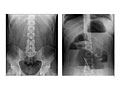

Abdominal X-Ray

Test OverviewAn abdominal

X-ray is a picture of structures and

organs in the belly (abdomen). This includes the

stomach, liver, spleen, large and small intestines, and the diaphragm, which is

the muscle that separates the chest and belly areas. Often two X-rays will be

ready the next day. Abdominal X-rayNormal: | The pictures made by the

X-rays show that the stomach, small and large bowel, liver, spleen, kidneys,

and bladder are normal in size, shape, and location. |